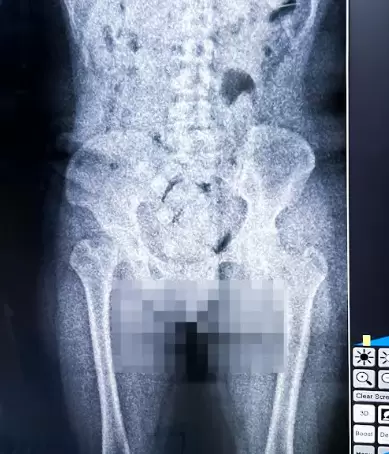

Resultado del escaner corporal practicado al hombre que trató de ingresar al país cocaína en cápsulas dentro de su cuerpo.

En ese marco, apelaron al control no intrusivo del body scan de la Aduana y advirtieron manchas en la zona abdominal, que podían indicar la presencia de cuerpos extraños en sus sistemas digestivos. Intervino la Fiscalía Federal de Tartagal y los ciudadanos del país vecino fueron internados para expulsar los bultos bajo supervisión médica.